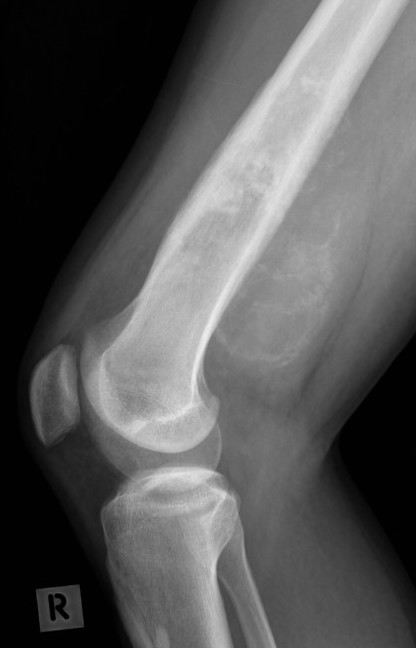

Xray

Typically metaphysis of long bones

- distal femur 35%

- proximal tibia 20%

- proximal humerus 10%

Can be diaphysis / axial skeleton

Features

- new bone formation / osteoid

- permeative cortical destruction

- wide zone of transition

- periosteal reaction

- soft tissue mass

Osteosarcoma of the distal femur